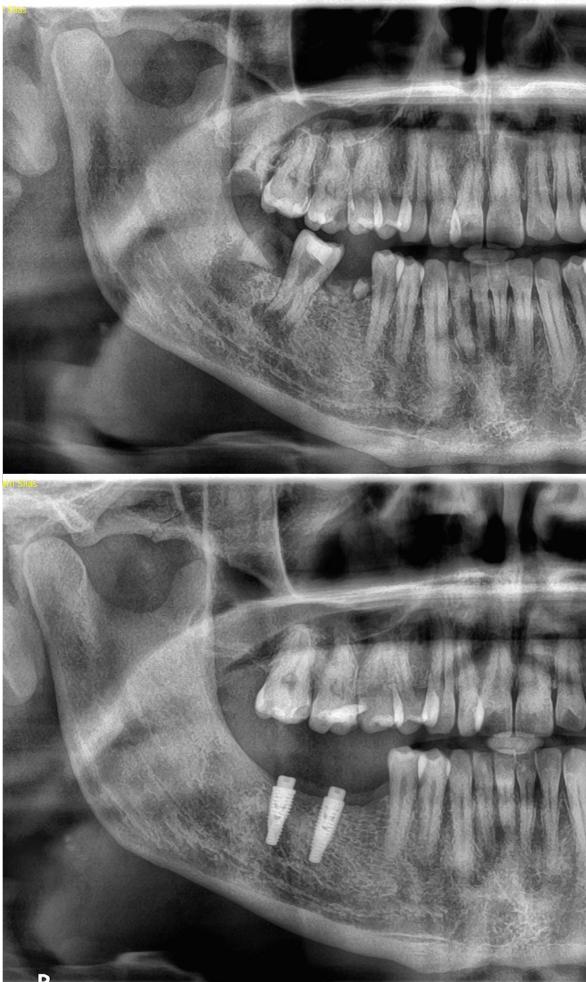

Efekt regeneracji kości po zastosowaniu PRF jest widoczny już po kilku miesiącach.

Przykład: Zdjęcie wykonane 8 miesięcy po zabiegu – odbudowa tkanki kostnej i poprawa warunków do leczenia implantologicznego.